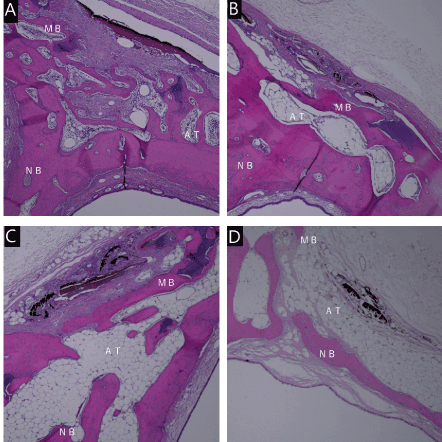

In group A, immature bone and limited osteoblastoma were observed in week 8. Mature bone tissue was observed more abundantly than in the other groups. Small quantities of inflammatory cells and carbonized tissues were observed, but adipose tissue was less abundant than in the other groups. Mature bone tissue was observed on week 16.

In group B, immature bone and limited osteoblastoma were observed in week 8, and mature bone tissue was also observed. Adipose tissues were found under carbonized tissue. Mature bone tissue was observed in week 16, but adipose tissue was less abundant than in week 8. In group C, immature bone and limited osteoblastoma were observed in week 8.

Mature bone tissue was observed on the side of the nasal cavity. More adipose tissue was found under the carbonized tissue than in groups A and B. Limited mature bone and adipose tissues were observed in week 16.

In group D, a small quantity of immature bone was observed in week 8. Adipose tissue was observed more abundantly under the carbonized tissue than in other groups. Mature bone was nearly absent, due to the heat. Limited mature bone and fat tissues were observed in the fat layer in week 16 (Figures 5A-D and 6A-D).

Figure 5. Micrograph 8 weeks after irradiation. Energy density of 88 J/cm2(A). Energy density of 220J / cm2(B). Energy density of 441J / cm2(C). Energy density of 61J / cm2(D). Hematoxylin-eosin staining, original magnification ×40, MB:mother bone, NB:new bone. AT:Adipose tissue

Figure 6. Micrograph 16 weeks after irradiation. Energy density of 88 J/cm2(A). Energy density of 220J / cm2(B). Energy density of 441J / cm2(C). Energy density of 61J / cm2(D). Hematoxylin-eosin staining, original magnification ×40, MB:mother bone, NB:new bone. AT:Adipose tissue